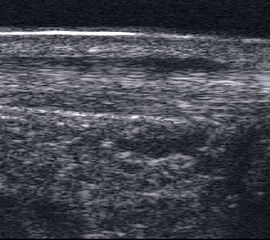

Achillessehne

Achillessehnenrupturen

Lagerung: Bauchlage, ggf. Sprunggelenk mittels Rolle unterlagert.

Schnittführung: LS über der Achillessehne, ggf. in leichter manueller Vorspannung der Achillessehne, damit diese parallel zum Schallkopf optimal eingestelt werden kann (Abb. 52).

Referenzstruktur: Direkt unter der Haut und der dünnen Subkutis liegt echogen und straff parallel die Achillessehne mit ihrem echogenen Peritendineum (Abb. 53), Tuber calcanei.